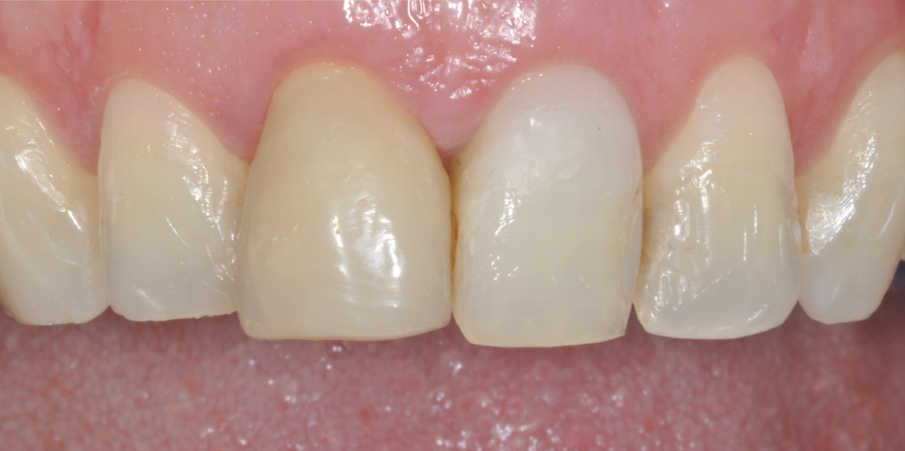

Fig. 12 - Trascorsi 7 mesi dalla chirurgia e dalla risoluzione del problema endodontico, si è proceduto con la preparazione a butt-joint del 12 e del 22 per ricevere due faccette e delle preparazioni complete a finire su 11 e 21 per le due corone monolitiche in disilicato.

Fig. 13 - Il manufatto protesico ultimato pre cementazione.

Fig. 14-16 - Il caso ultimato.